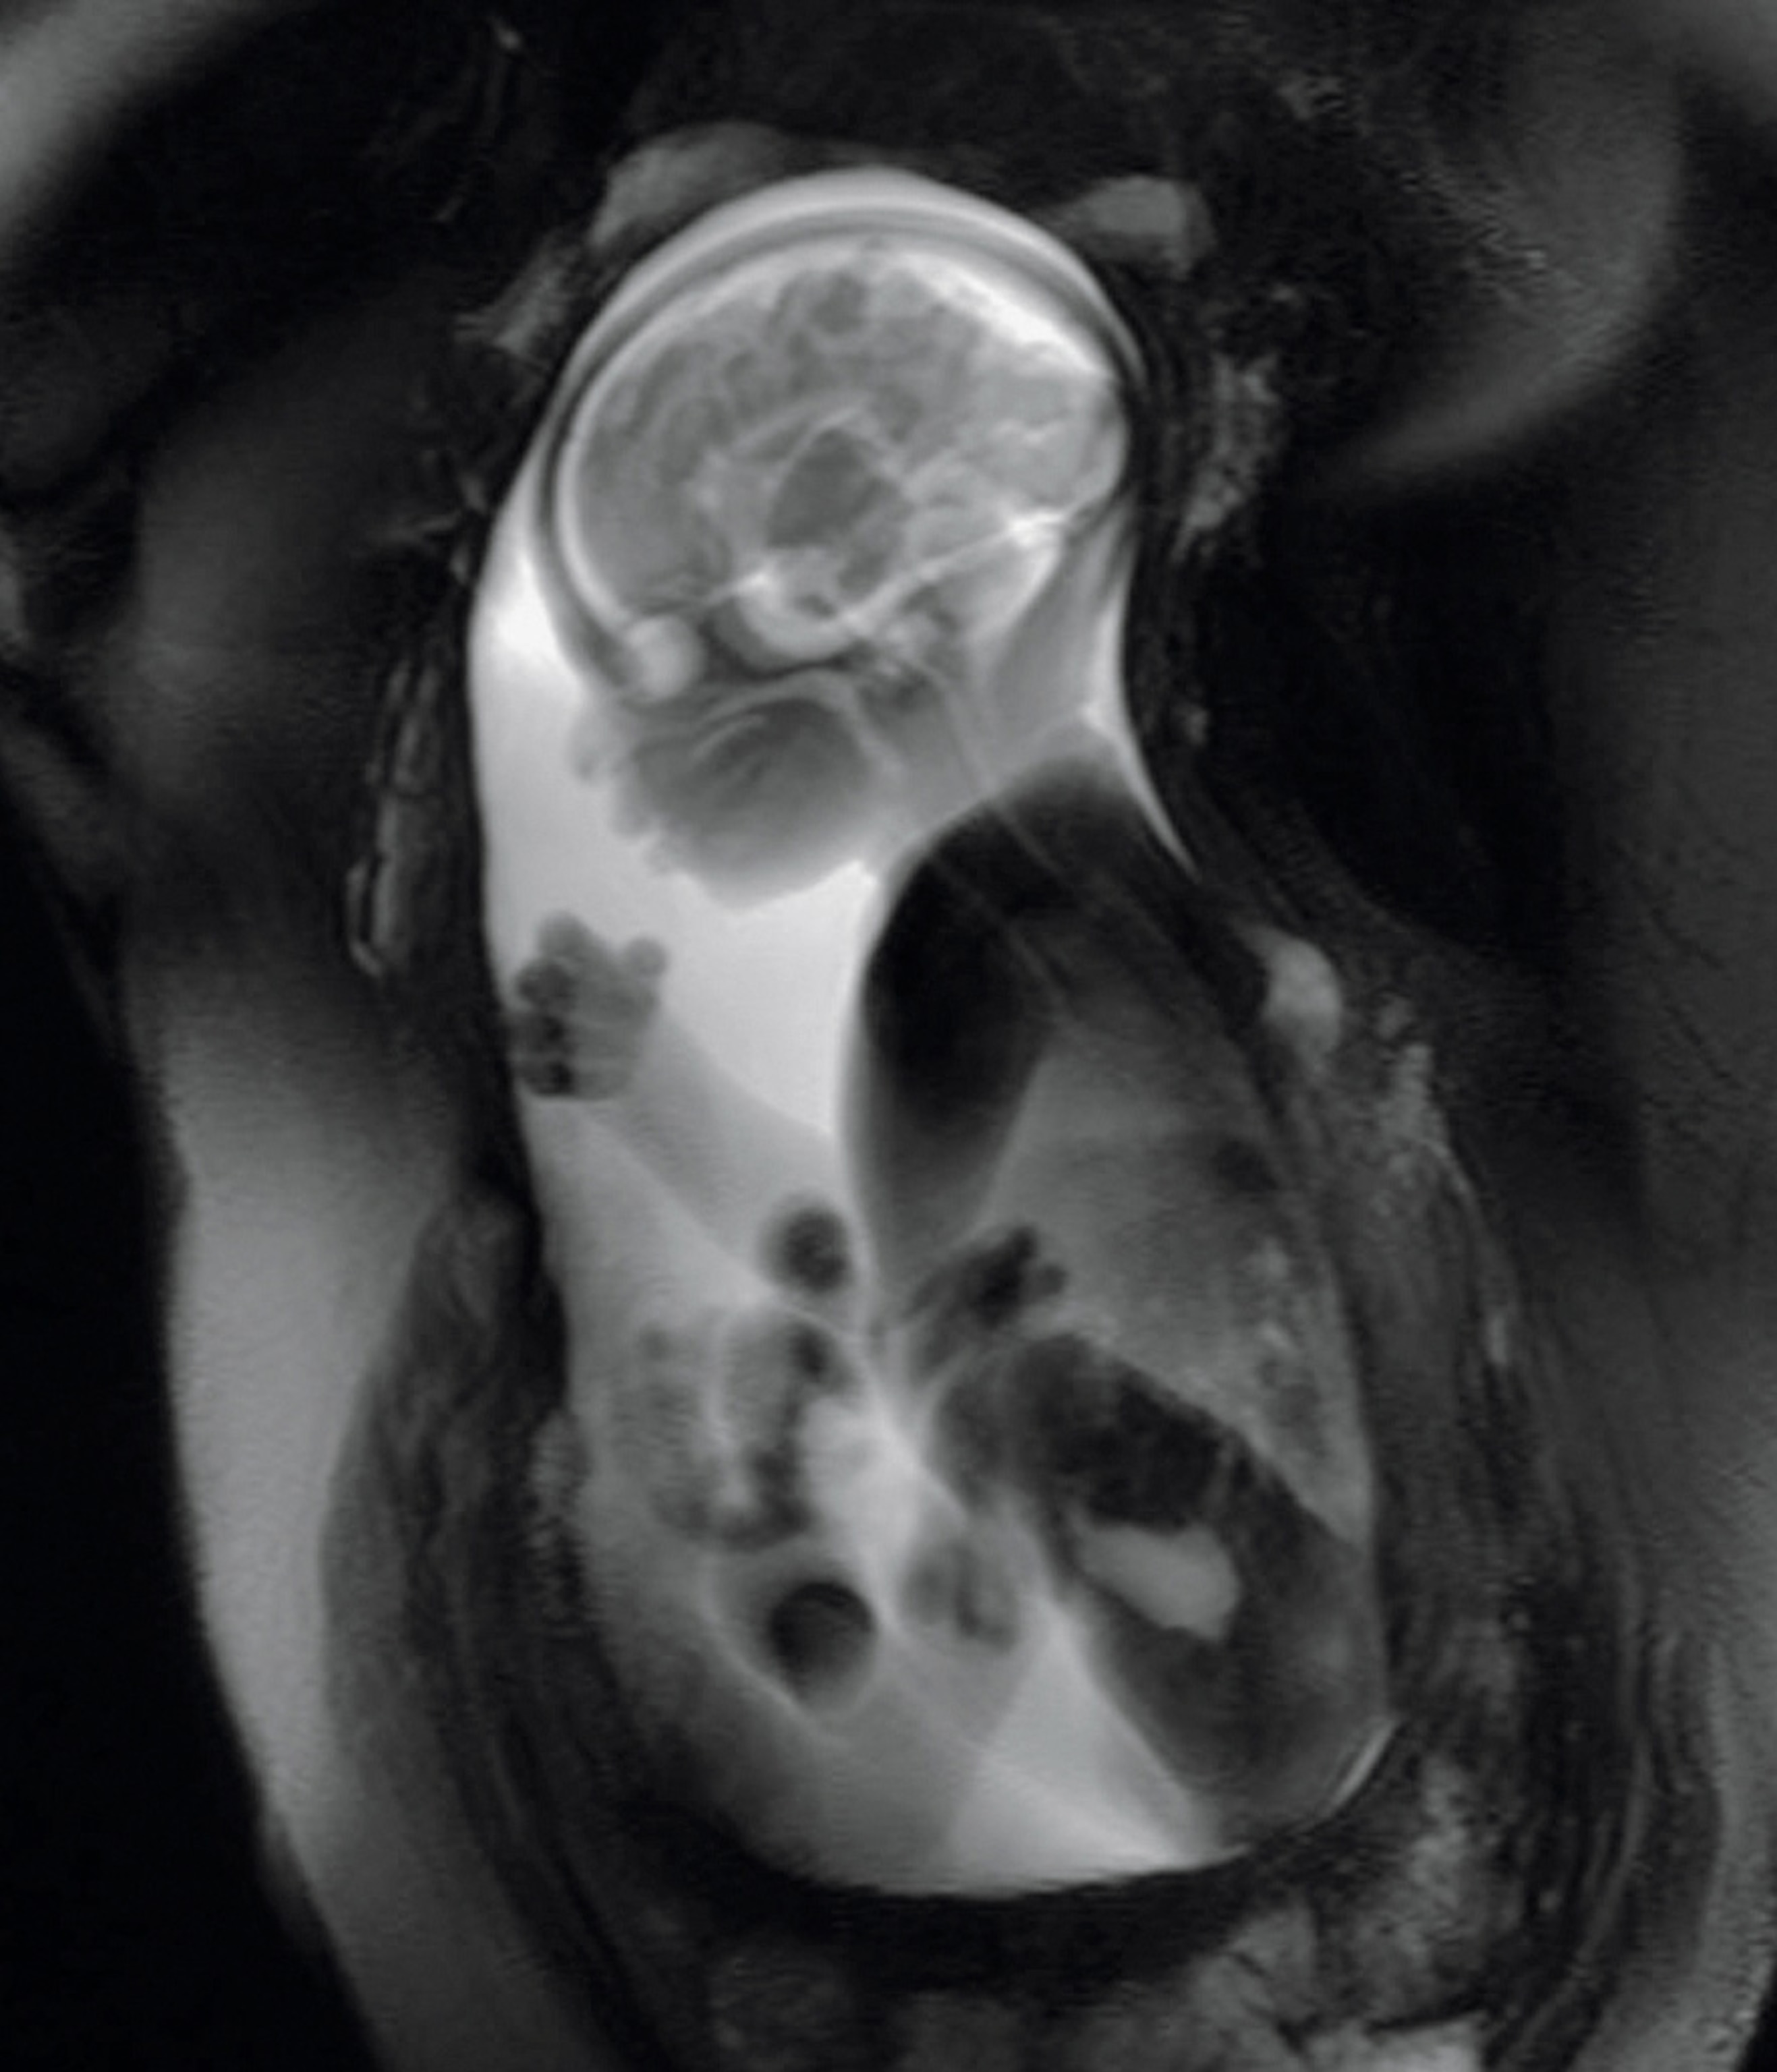

Diagnosis in utero is on the far horizon, says pediatric neuroscientist Moriah Thomason, whose research aims to solve some of the mysteries of the fetal brain. At Detroit’s Wayne State University, she and her team use MRI technology to check the growth of a fetus’s brain and map the neural connectivity within it, creating a groundbreaking snapshot of how well the organ is functioning.

They focus on cases where there’s danger of premature birth, Thomason says, because “we know that preterm children are at higher risk for developmental delays.” Such delays are often blamed on stress or lack of oxygen during birth. Thomason’s work suggests impairment may start in the womb, possibly with an undetected infection.